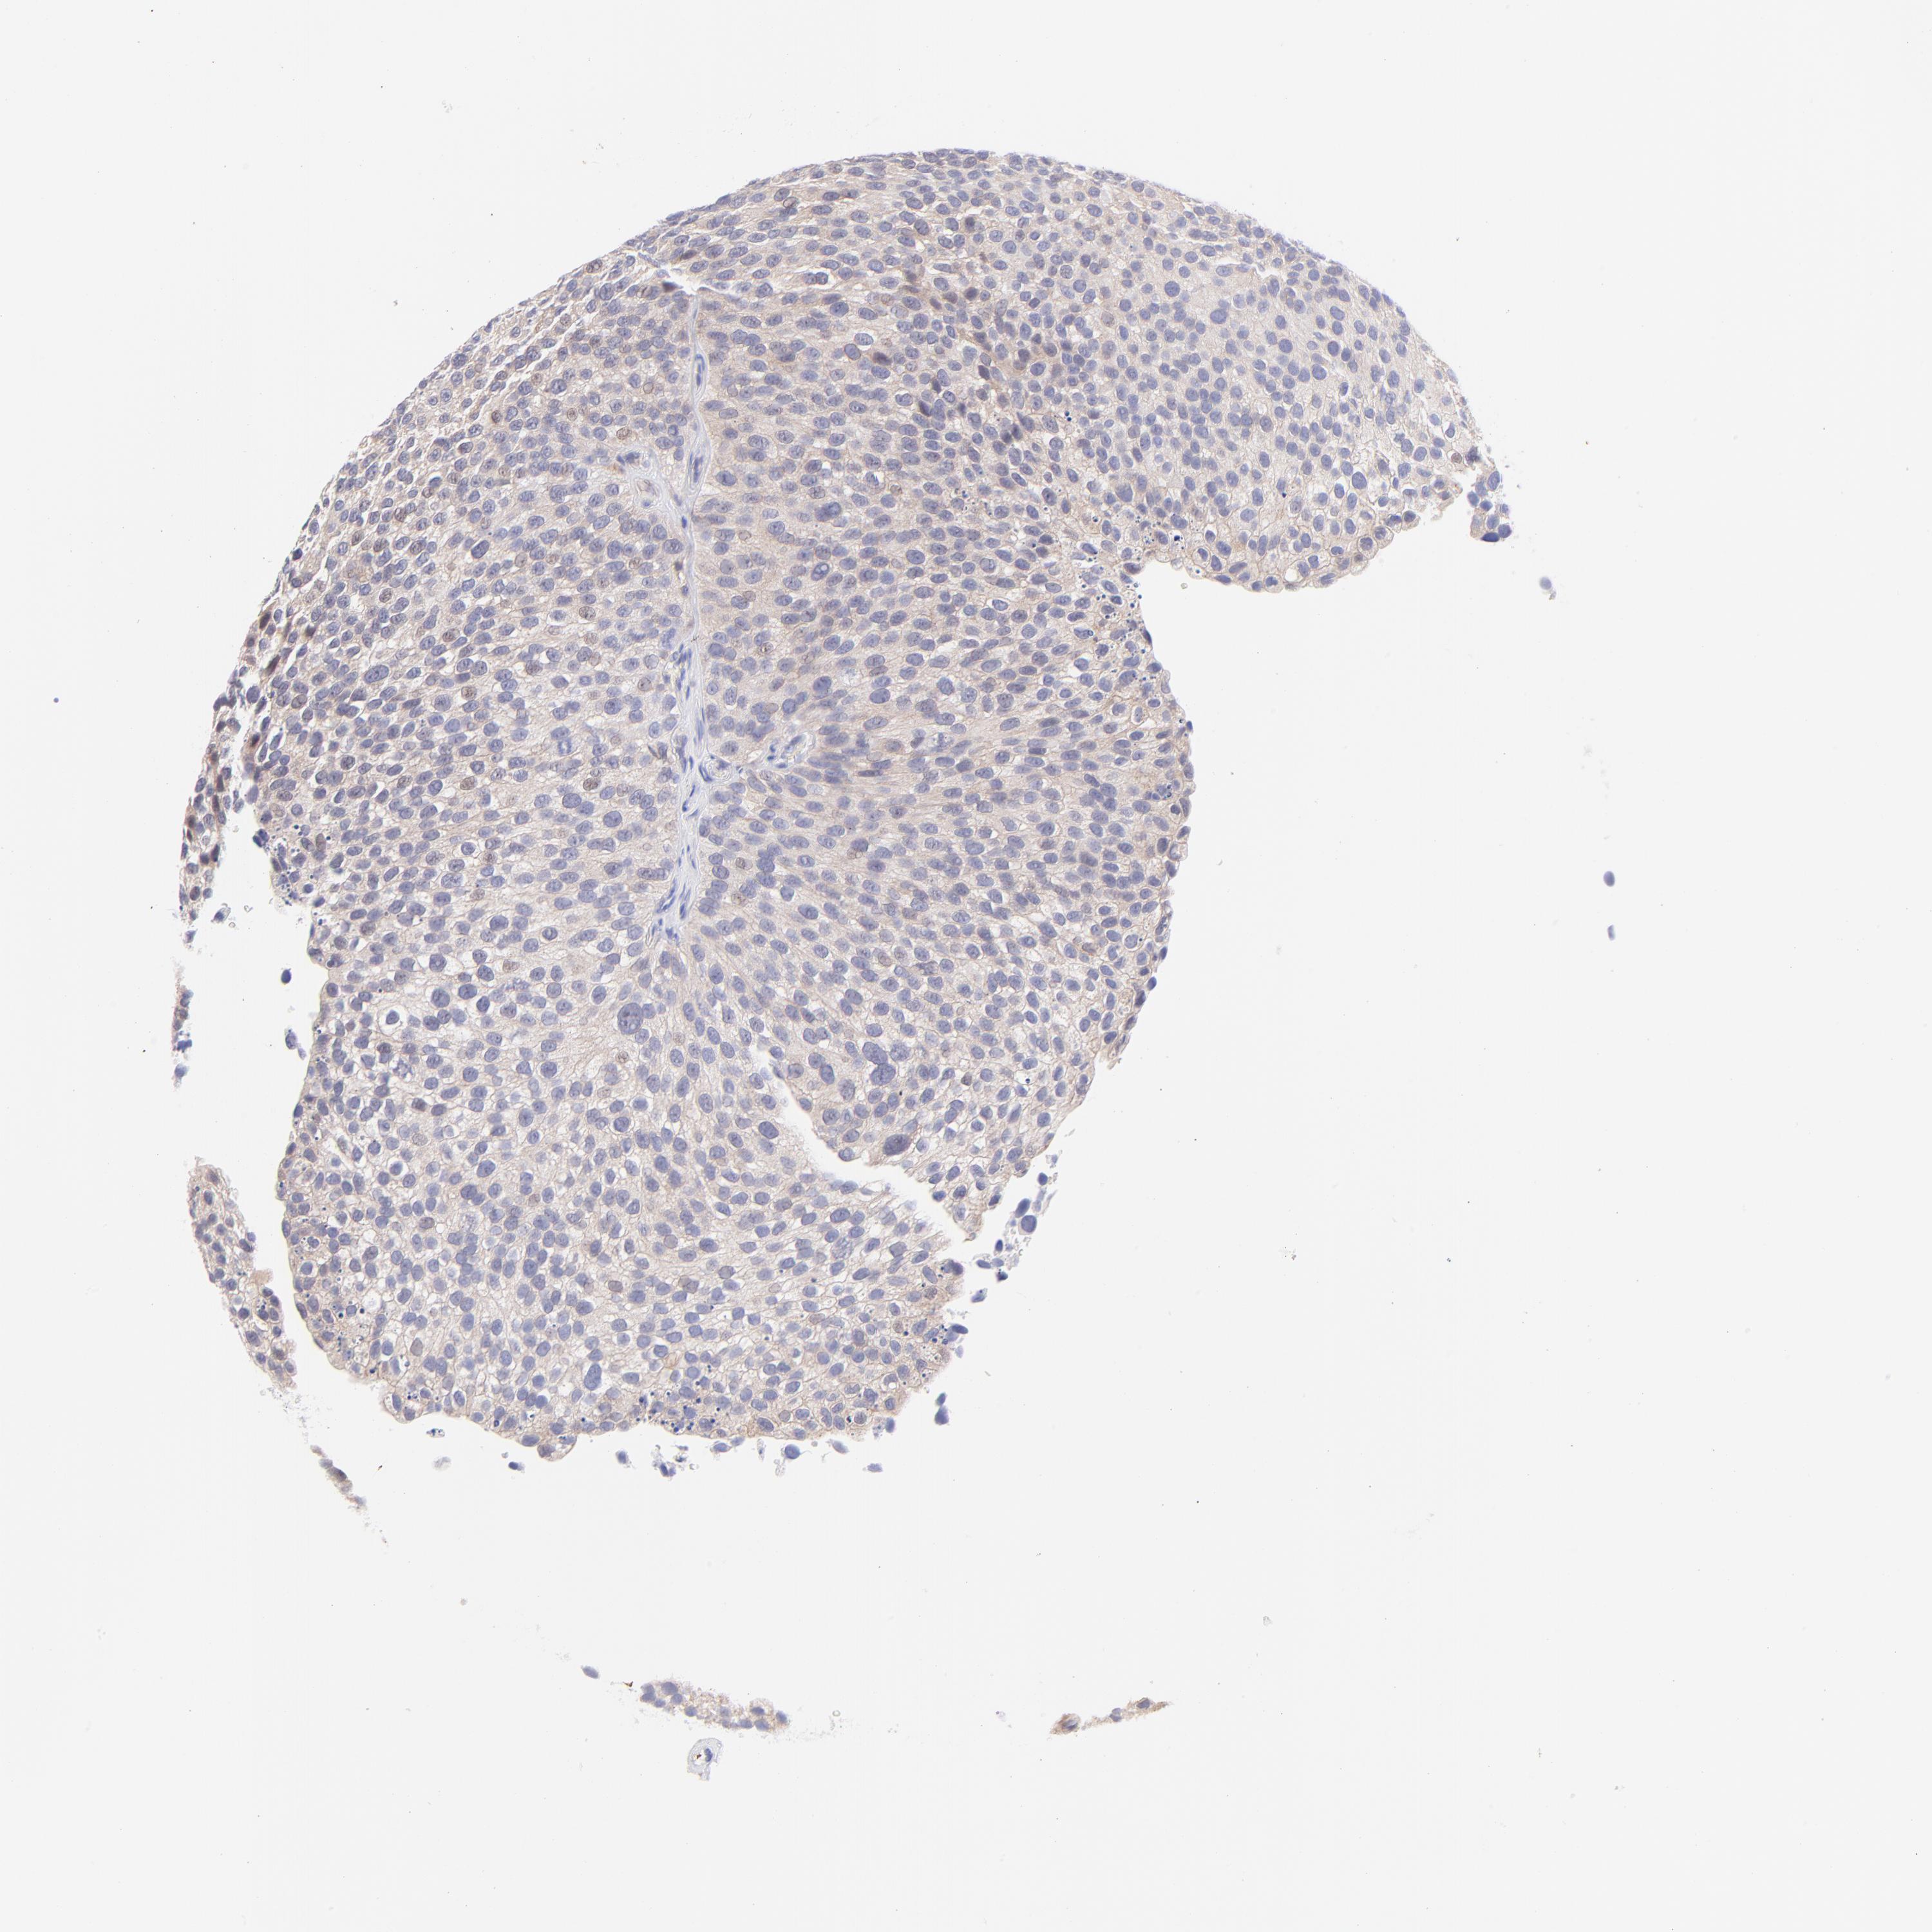

UROTHELIAL CANCER - Protein expressioni

A mouse-over function shows sample information and annotation data. Click on an image to view it in a full screen mode. Samples can be filtered based on level of antibody staining by selecting one or several of the following categories: high, medium, low and not detected. The assay and annotation is described here.

Note that samples used for immunohistochemistry by the Human Protein Atlas do not correspond to samples in the TCGA dataset.

Antibody stainingi

Antibody staining in the annotated cell types in the current human tissue is reported as not detected, low, medium, or high, based on conventional immunohistochemistry profiling in selected tissues. This score is based on the combination of the staining intensity and fraction of stained cells.

Each image is clickable and will lead to virtual microscopy that enables deeper exploration of all samples and also displays staining intensity scores, fraction scores and subcellular localization as well as patient and tissue information for each sample.

Antibody HPA003155

Staining

High

Medium

Low

Not detected

Intensity

Strong

Moderate

Weak

Negative

Quantity

>75%

75%-25%

<25%

None

Location

Nuclear

Cytoplasmic/membranous

Cytoplasmic/membranous,nuclear

Urothelial carcinoma, High grade

Urothelial carcinoma, Low grade